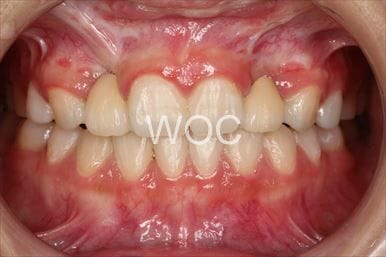

八重歯・叢生マウスピース型(カスタムメイド)矯正装置(インビザライン)

マウスピース型(カスタムメイド)矯正装置(インビザライン)を希望。ガタガタ(叢生)が強く上顎両側第一小臼歯抜歯か非抜歯のボーダーラインケースだったが、装置装着時間の協力も良く非抜歯で終了となりました。

- 年齢:35歳女性

- 主訴:ガタガタ

- 基本矯正料金:88万円

- 治療期間:2年6ヶ月

- 非抜歯

-